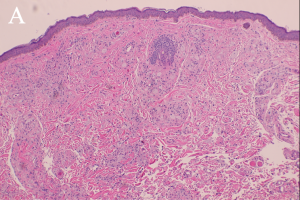

"Xanthoma” is a broad term referring to a tumor that is characterized by the presence of xanthoma cells, also called foam cells (Images 1A, 1B). These lipid-laden macrophages contain elevated levels of carotene, which give the lesions their yellow color. The most common type of xanthoma encountered in ophthalmic practice is xanthelasma palpebrarum,[1] which are superficial xanthomas found on the eyelids (Images 2A, 2B). Xanthomas of bone involving the orbit have been reported[3][4] and xanthomas in orbital soft tissue have been rarely reported (Images 6 and 7).[5] Xanthoma verrucum (oral), xanthoma tuberosum (articular), and xanthoma planum (dermal) are other examples of xanthomas found in specific regions.

Xanthomatous lesions consist of mononuclear macrophage-like cells, foam cells, and multinucleated giant cells within layers of histiocytes (Images 1A, 1B). The xanthoma cells are positive for CD68 and vimentin.[19] There is often a surrounding lymphocytic infiltrate.